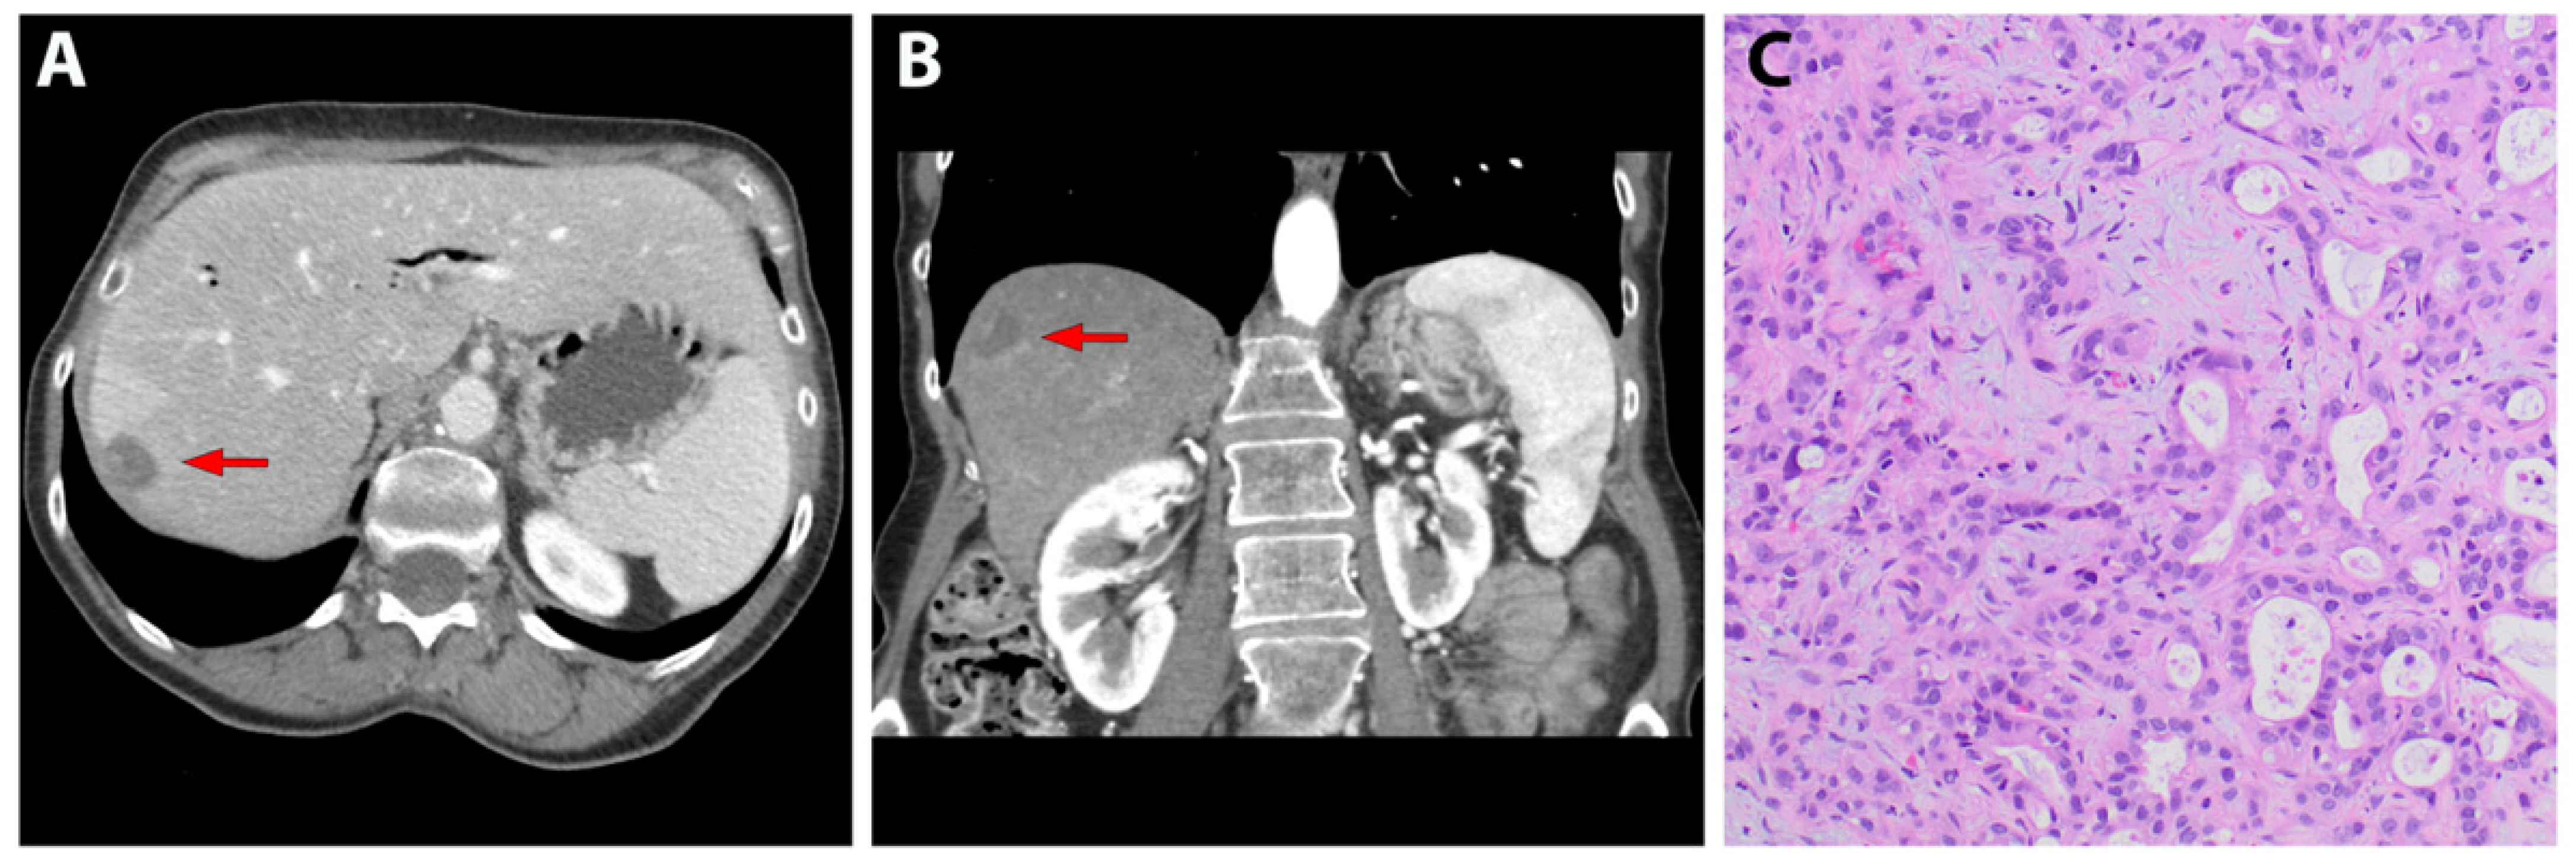

3.1. Patient-Derived Liver Metastasis of Pancreatic Cancer